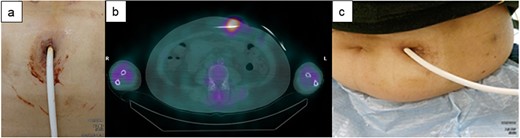

A 60-y-old man with ischemic cardiomyopathy underwent LVAD implantation (HeartMate II™, Abbott Co., Abbott Park, IL, USA) 2 y before being admitted to our hospital because of pain and skin redness above the umbilicus. He had no skin induration and tenderness at the DLES; however, redness, local increase in temperature, and skin induration and tenderness were noted above the umbilicus (Fig. 3a). As the inflammatory area was far from the DLES, surgical debridement and associated relocation of the exit site were considered. 67Ga SPECT showed a high signal up to 5 cm inside the DLES (Fig. 3b). The empirical antibiotics were administered intravenously after collection of cultures of exit site and drained fluid. First, the catheter cleaning method via the DLES was executed, daily bedside debridement with 10% silver nitrate solution was performed via the DLES to eliminate the contaminated tissue for about 1 week. In this patient, the DLES and spot with redness were distant, and it was suspected that the infected granulation tissue affected the discharge of the exuded solution. Therefore, monofilament nylon threads were inserted for continuous drainage (Fig. 3a). Simultaneously, daily irrigation using an intravenous indwelling catheter was continued with a 1000-ml saline solution for about 1.5 months (Fig. 2e). Although repeated culture of drained fluid did not detect the definitive pathogenic bacterium, intravenous antibiotics were used for about 6 weeks but were then switched to oral antibiotics. The spot with redness healed, and the patient was discharged from the hospital 2 months after admission (Fig. 3c). This patient was readmitted for a similar DLI 4 months later and was treated with the same catheter method for about 3 weeks. Then, DLI did not reoccur until 1.5 y later.

The clinical course of development of the DLI in Case 1. (a) There was some distance between the DLES and the spot with redness and induration. (b) 67Ga SPECT shows high signalization within reach of the cotton swab and intravenous catheter from DLES. (c) The spot with redness and induration healed after treatment with this catheter method.